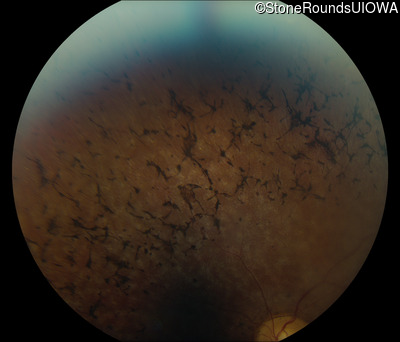

Fundus Photography - Left - 20/32 -1

Exemplar

Fundus Photography - Left - 20/30